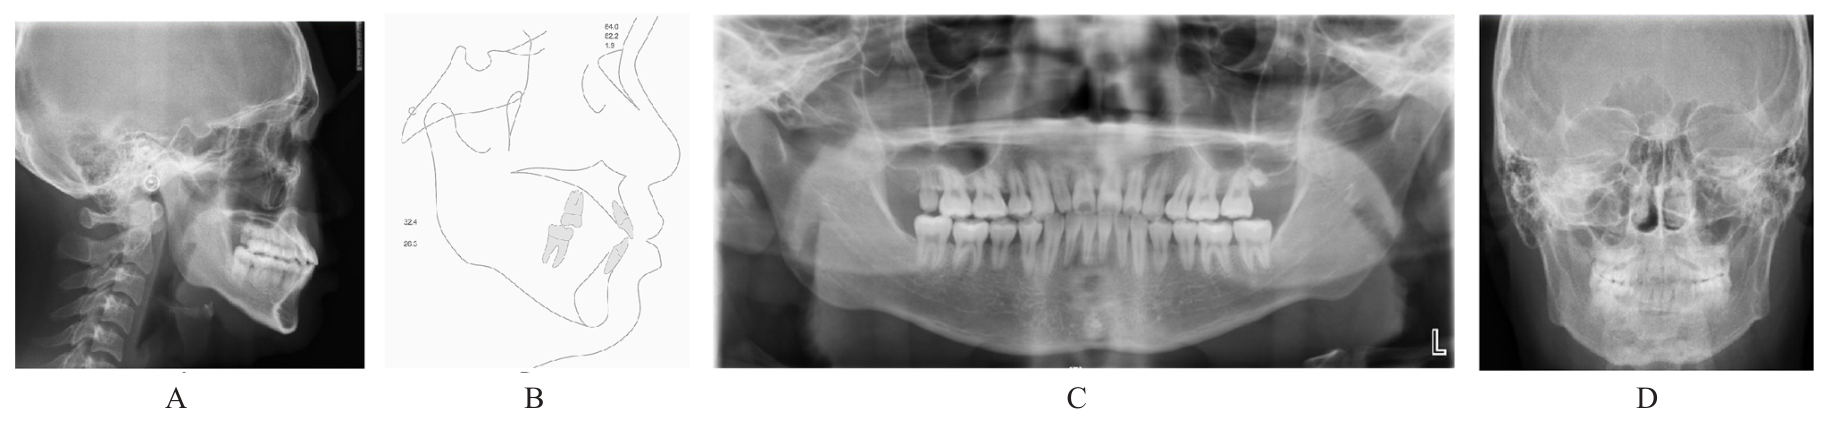

Grade Ⅲ open bite complicated with tongue hypertrophy treated by mandibular incisor extraction:A case report and literature review

Tab.1

Cephalometric detection analysis of patient with grade Ⅲ open bite complicated with tongue hypertrophy before and after treatment"

| Measurement | Normal (x±s) | Pretreatment | Posttreatment |

|---|---|---|---|

| SNA (°) | 82.8±4.0 | 84.1 | 83.8 |

| SNB (°) | 80.1±3.9 | 80.7 | 82.2 |

| ANB (°) | 2.7±2.0 | 3.4 | 1.6 |

| MP-SN (°) | 32.5±5.2 | 35.2 | 32.4 |

| U1-SN (°) | 105.7±6.3 | 116.9 | 111.8 |

| U1-NA (mm) | 5.1±2.4 | 6.7 | 6.6 |

| U1-NA (°) | 22.8±5.7 | 32.8 | 28.1 |

| L1-MP(°) | 92.6±7.0 | 105.7 | 93.4 |

| L1-NB (mm) | 6.7±2.1 | 8.7 | 6.8 |

| L1-NB (°) | 30.3±5.8 | 41.6 | 28.0 |

| U1-L1 (°) | 125.4±7.9 | 102.1 | 122.4 |

| Wits (mm) | -1.1±2.0 | -2.4 | -2.0 |

| APDI (°) | 86.0±4.0 | 80.8 | 85.5 |

| ODI (°) | 73.3±5.9 | 66.0 | 68.0 |

| S-Go (mm) | 80.0±4.0 | 79.7 | 82.1 |

| N-Me (mm) | 112.0±7.0 | 118.9 | 119.5 |

| S-Go/N-Me (%) | 63.0±2.0 | 67.0 | 68.7 |